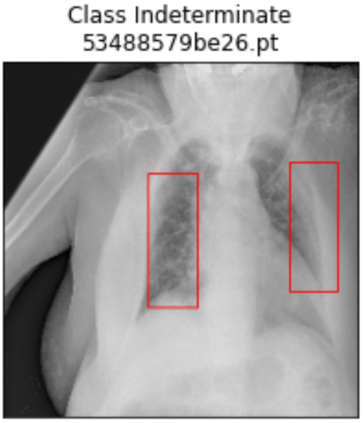

Deep learning technologies have already demonstrated a high potential to build diagnosis support systems from medical imaging data, such as Chest X-Ray images. However, the shortage of labeled data in the medical field represents one key obstacle to narrow down the performance gap with respect to applications in other image domains. In this work, we investigate the benefits of a curricular Self-Supervised Learning (SSL) pretraining scheme with respect to fully-supervised training regimes for pneumonia recognition on Chest X-Ray images of Covid-19 patients. We show that curricular SSL pretraining, which leverages unlabeled data, outperforms models trained from scratch, or pretrained on ImageNet, indicating the potential of performance gains by SSL pretraining on massive unlabeled datasets. Finally, we demonstrate that top-performing SSLpretrained models show a higher degree of attention in the lung regions, embodying models that may be more robust to possible external confounding factors in the training datasets, identified by previous works.